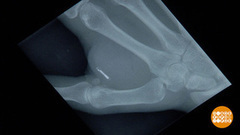

Кошка Светланы Демчук недавно сбежала из дома. Вернулась только через три дня. После этого случая хозяйка решила мурку чипировать.

Каждый чип имеет свой индивидуальный номер, который вносят в базу данных, где указывают информацию о животном и его владельце – имя, адрес и телефон. «Российская база данных интегрирована в международную сеть, - заявила ветеринарный врач Наталья Марченко. - Даже если ваше животное потеряется за границей, там вы тоже его найдете».